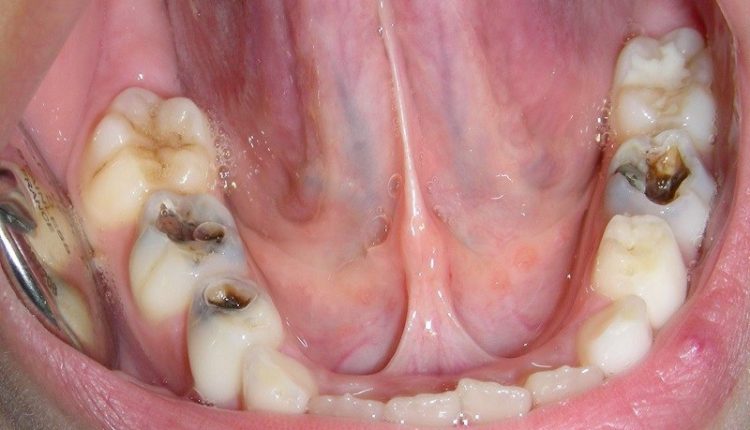

A veces pensamos que las caries fueron una etapa de la infancia porque comíamos muchos dulces, sin embargo en nuestra etapa de adultos también están presentes y por ende también en los niños, por lo que se debe tener cuidado puesto que estas pueden convertirse en infecciones graves e incluso pueden causar la muerte.

Si, como lo leíste, de acuerdo con la coordinadora de Investigación del Servicio del Estomatología del Hospital General de México, Claudia Bravo, si las caries no se atienden, la calidad de vida de las personas se puede ver afectada por el dolor y la sensibilidad dental que estas ocasionan, pero de igual forma pueden llevar a la muerte.

Es por ello que dio a conocer que las complicaciones que se tornan graves de las caries es la angina de Ludwing (infección grave y de que rápidamente progresa) ocasionada por abscesos dentales, y la endocarditis ( “la membrana que recubre el interior de las cavidades del corazón”) la cual es originada por la propagación de las “bacterias de la cavidad oral hasta el corazón”; información adn40.